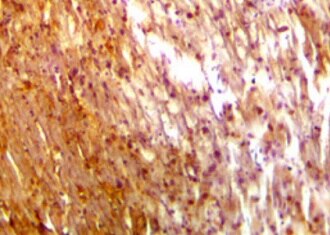

Myoglobin in Human Heart. Myoglobin was detected in immersion fixed paraffin-embedded sections of human heart using Mouse Anti-Human Myoglobin Monoclonal Antibody (Catalog # MAB97202) at 1.7 µg/mL for 1 hour at room temperature followed by incubation with the Anti-Mouse IgG VisUCyte™ HRP Polymer Antibody (Catalog # VC001). Tissue was stained using DAB (brown) and counterstained with hematoxylin (blue). Specific staining was localized to sarcoplasm. View our protocol for IHC Staining with VisUCyte HRP Polymer Detection Reagents.